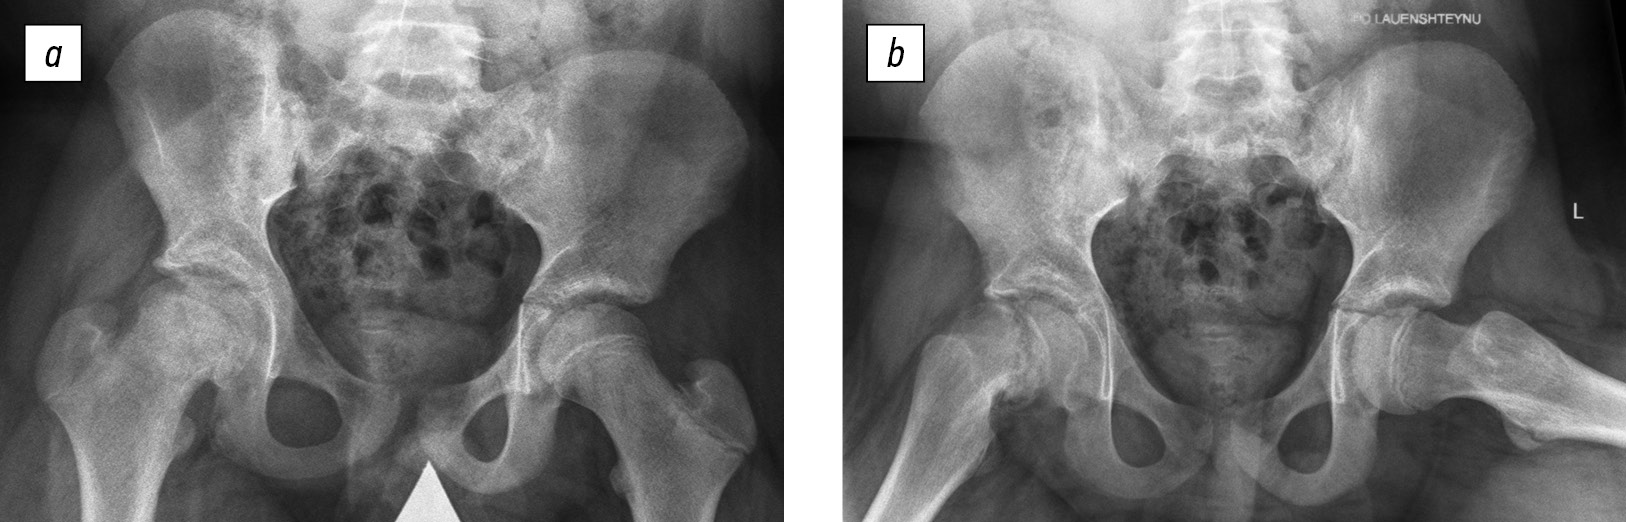

The clinical study did not differ from the classical technique used in patients with orthopedic pathology of the hip joints. All patients underwent radiography of the hip joints in the anteroposterior projection and Lauenstein projection in the supine position, a panoramic radiograph of the lower extremities, and a lateral panoramic radiograph of the spine, including the femoral heads in the standing position. On radiographs taken in the supine position (Fig. 1), the values of the projection caput–collum–diaphyseal angle, projection epiphyseal–diaphyseal angle, and epiphyseal angle were determined, and signs of partial, and complete synostosis at the level of the epiphyseal growth zone were excluded. In addition, the posterior and downward epiphyseal displacement angles were evaluated on the displacement side, and the absence of the epiphyseal displacement was confirmed on the contralateral side. The posterior epiphyseal displacement angle was calculated from the difference in the epiphyseal angles in the joint without (individual norm) and with displacement. The downward displacement angle was calculated by the difference between the caput–collum–diaphyseal angle and the epiphyseal–diaphyseal angle in the joint with displacement. On radiographs taken in the standing position (Fig. 2), indicators of the magnitude of thoracic kyphosis and lumbar lordosis (according to Cobb), pelvic incidence (PI), sacral slope (SS), pelvic tilt (PT), sagittal vertical axis (SVA), and spinosacral angle (SSA) were determined.

Fig. 1. Radiographs of the hip joints in the anteroposterior projection (a) and Lauenstein projection (b) of patient A., aged 13 years 2 months, with slipped capital femoral epiphysis, posterior epiphyseal displacement by 62° and downward displacement by 4° on the right, and no displacement (pre-slip stage) on the left